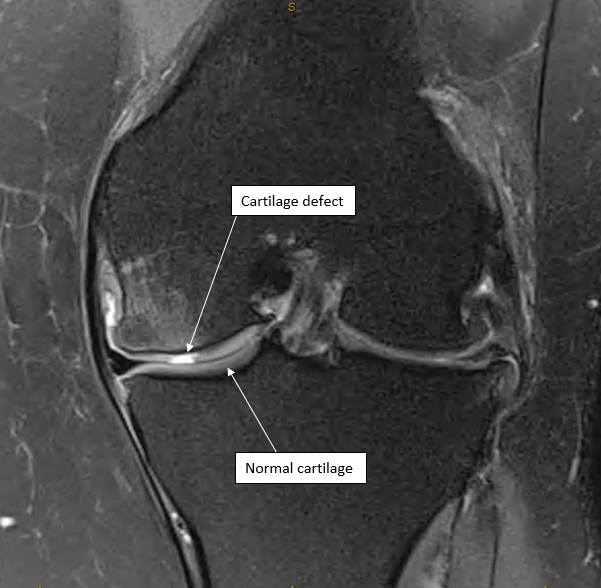

Most injuries can be treated initially with some anti-inflammatory medication and physiotherapy. If the knee is jamming or locking up, or is unstable these are signs that you should seek the opinion of an orthopaedic surgeon who would probably want you to get an MRI scan. The MRI scan will help show the size and position of the cartilage defect and can also show if there is a loose piece of cartilage floating around which would need to be removed.